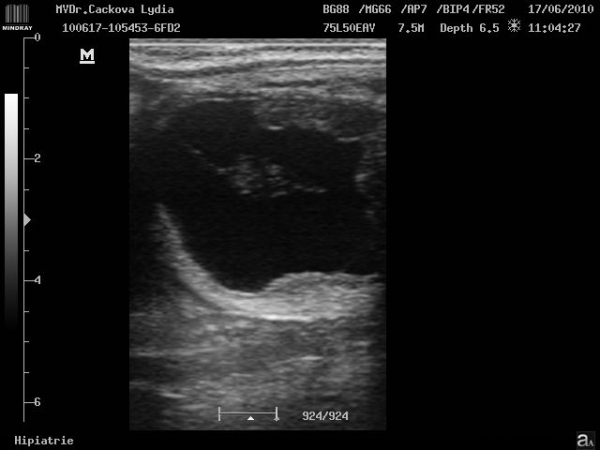

embryo kolem 21.dne